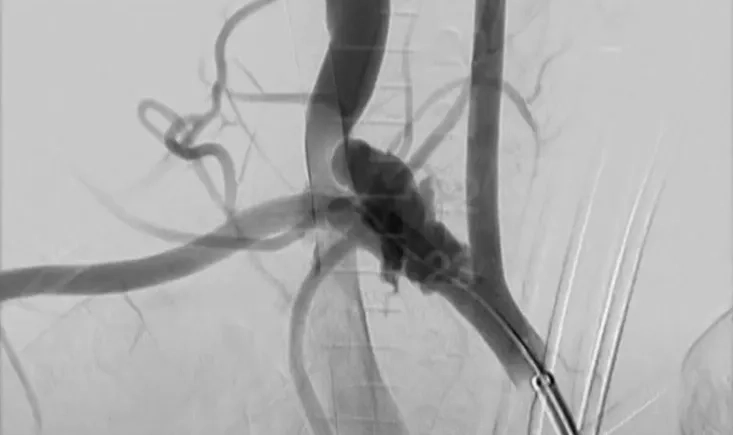

A 73-year-old man with major cardiovascular risk factors presented with acute pain and was diagnosed with a…